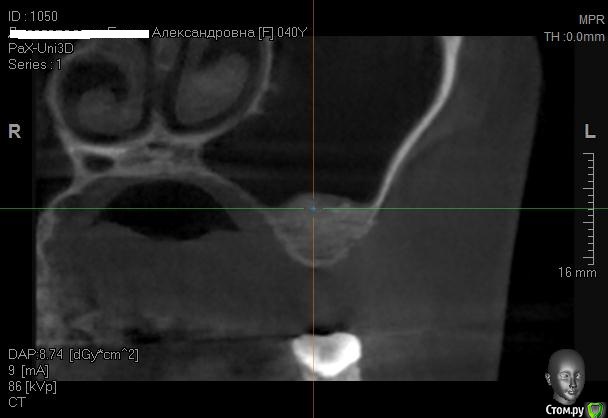

Kostoprav Опубликовано 12 июня, 2014 Автор Поделиться Опубликовано 12 июня, 2014 одновременно поставить -высоты кости не хватило ? 1-2 мм , я рисковать не захотел. 2 Ссылка на комментарий